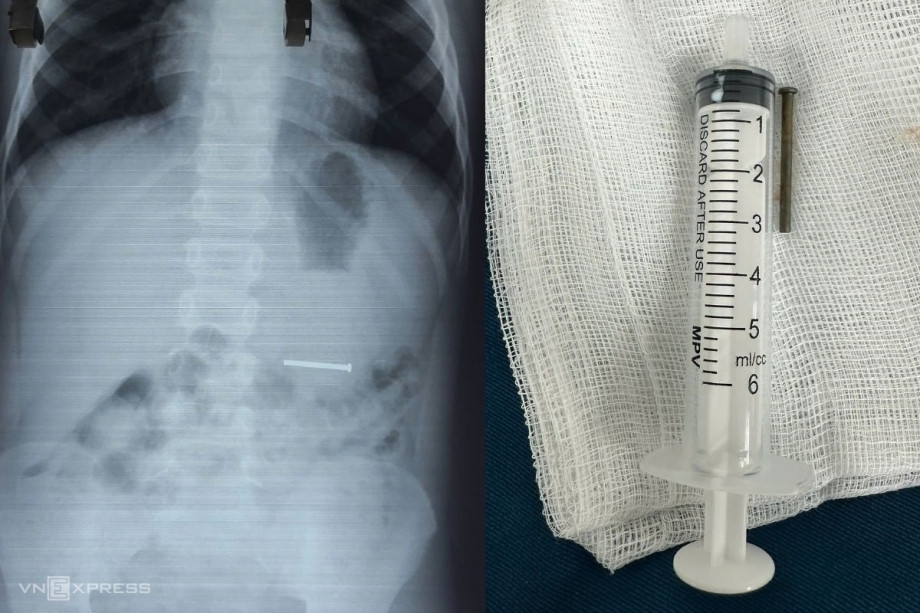

Bé trai được cấp cứu tại bệnh viện nhưng đã không qua khỏi. (Ảnh: Sohu)